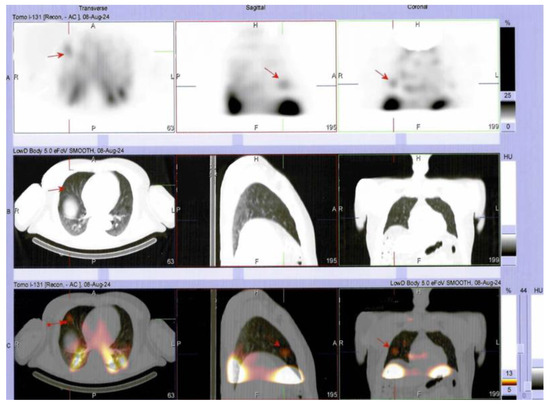

Multilayered Insights into Poorly Differentiated, BRAFV600E-Positive, Thyroid Carcinoma in a Rapidly Developing Goiter with Retrosternal Extension: From En “Y” Cervicotomy to SPECT/CT-Positive Lung Metastases

Sima, O.-C.; Cucu, A.-P.; Terzea, D.; Nistor, C.; Vasilescu, F.; Eftimie, L.-G.; Ciobica, M.-L.; Costachescu, M.; Carsote, M. Multilayered Insights into Poorly Differentiated, BRAFV600E-Positive, Thyroid Carcinoma in a Rapidly Developing Goiter with Retrosternal Extension: From En “Y” Cervicotomy to SPECT/CT-Positive Lung Metastases. Diagnostics 2025, 15, 2049. https://doi.org/10.3390/diagnostics15162049